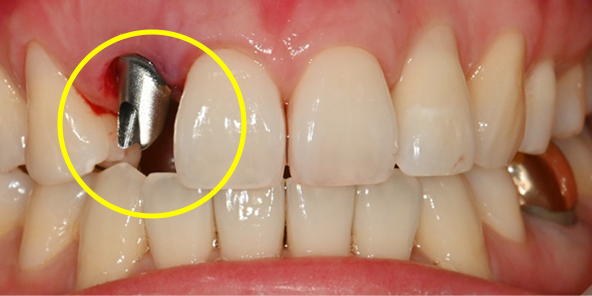

기존 임플란트

임플란트를 식립하고 동시에 보철물도 완성해드립니다.

내원 당일 이루어지는 임플란트 기술력! 하루 완성 임플란트는 당일에 식립하고

임시 보철물까지 완성됩니다.